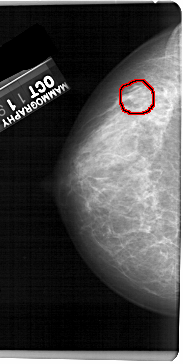

A_1432_1.LEFT_CC

LEFT_CC LINES 5446 PIXELS_PER_LINE 2731 BITS_PER_PIXEL 12 RESOLUTION 43.5 OVERLAY

FILE: A_1432_1.LEFT_CC.OVERLAY

TOTAL_ABNORMALITIES 1

ABNORMALITY 1

LESION_TYPE MASS SHAPE OVAL MARGINS OBSCURED

ASSESSMENT 4

SUBTLETY 3

PATHOLOGY BENIGN

TOTAL_OUTLINES 1

BOUNDARY